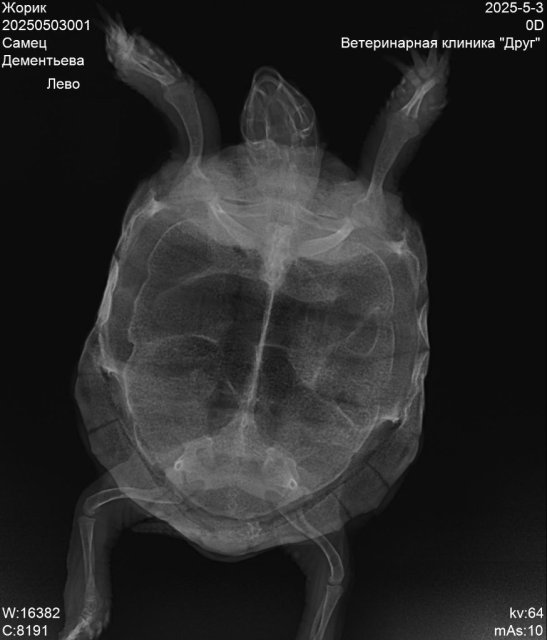

Пермь. Сухопутная черепаха. Террариум самодельный, длина 85см, ширина40, высота 40.лампа накаливания обычно работает в зоне прогрева 12часов.ультрафиолетовая лампа тоже 12часов    reptispa desert 10.0 uvb10. Грунт кокосовый субстрат перемешаный с речным песком. Температура под лампой 30-32гр.Летом кормим травой одуванчик, подорожник, клевер. Зимой салат, кабачок, огурец. Живёт у нас 9лет.вес 400гр., панцирь по длине 15см.заболела в конце марта. Чихала, был насморк, вялость. Лечили энрофлон аскорбинка, кальций, элеовит это было по рекомендации онлайн ветеринара. Потом еще назначали ингаляции с флуимуцилом это уже назначили в клинике друг, врач Бажина.Сейчас при еде выходит пена изо рта и носа.

20250503001_Жорик_Дементьева_20250503092325236.jpg

20250503001_Жорик_Дементьева_20250503092325086.jpg

20250503001_Жорик_Дементьева_20250503092324931.jpg

лечение когда закончили и снимки эти когда делали?

Лечение закончили в середине мая ингаляции с флуимуцилом. Рентген делали после лечения антибиотиком, перед лечением ингаляциями

@Галина М по-хорошему вам нужно снова на очный приём и делать новый рентген. Это очень сильная пена и даже если это из желудка - это очень не нормально. А из лёгких и подавно.